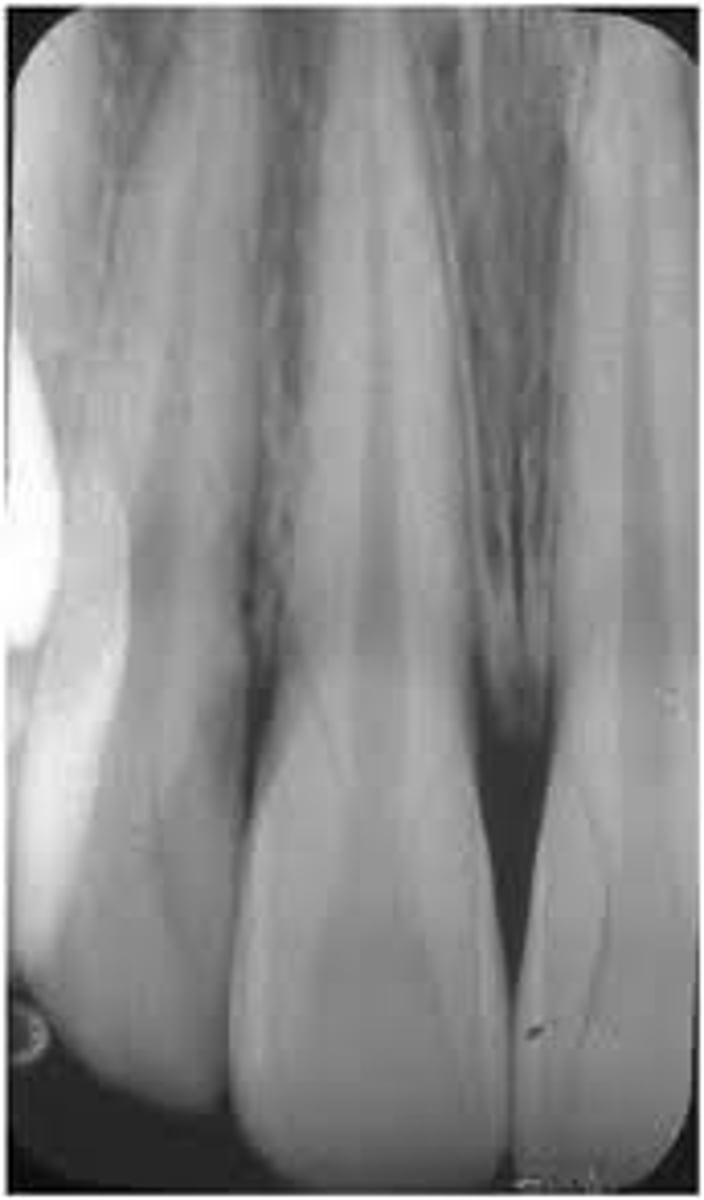

What is elongation?

A condition caused by insufficient vertical angulation